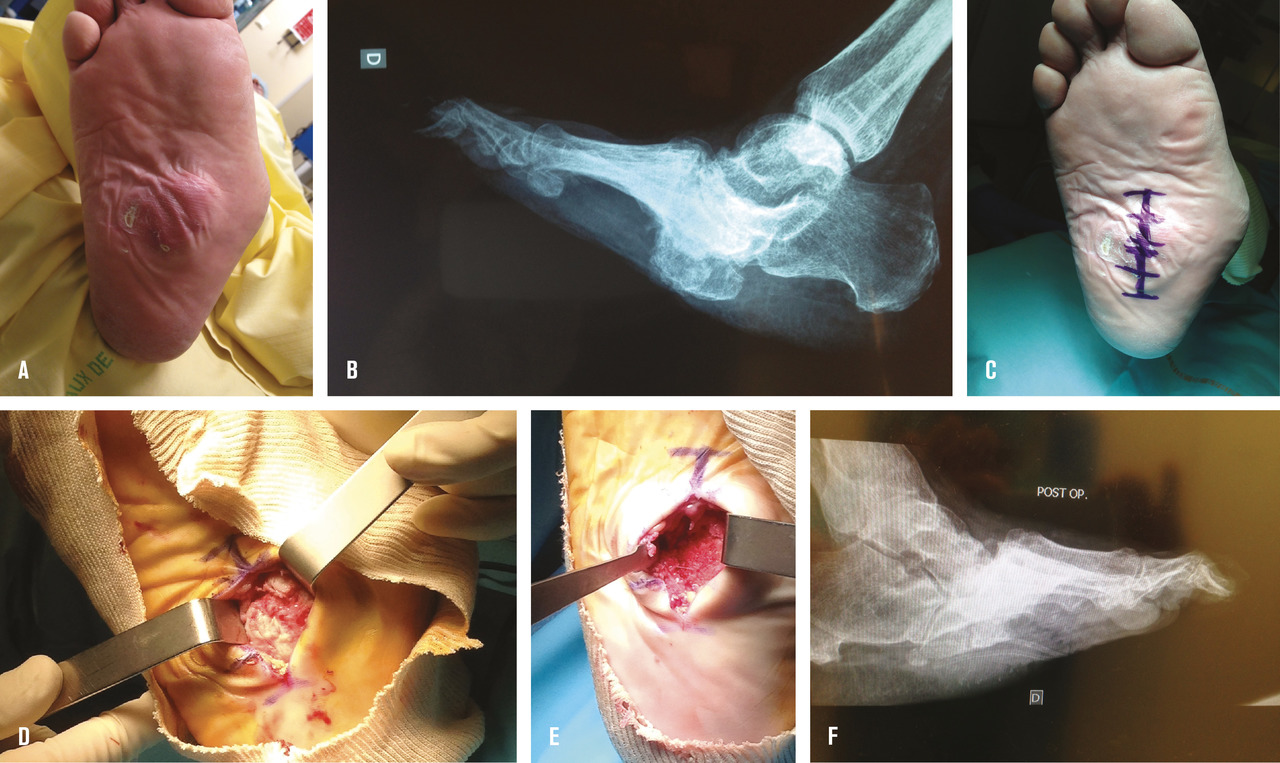

L’ostéite et les ostéo-arthrites du médio-pied, liées aux déformations du pied dans le cadre d’une neuro-arthropathie de Charcot, peuvent bénéficier de différents traitements chirurgicaux. Le plus simple consiste à réséquer la saillie responsable du conflit, il s’agit d’une ostectomie (fig. 3 ). Elle permet de traiter l’infection et la cause. Elle s’envisage idéalement sur un pied de Charcot au stade chronique avec déformation fixée. En cas d’ostéo-arthrite sur pied de Charcot avec articulation infectée hypermobile, on préfère une chirurgie d’excision de l’infection osseuse associée à une stabilisation articulaire afin d’obtenir un pied stable et plantigrade. Cette stabilisation peut se faire soit par un fixateur externe circulaire, soit avec une synthèse interne. Les modalités de ces traitements sont variables selon les habitudes des équipes chirurgicales, la chirurgie se faisant en un ou deux temps, le premier temps traitant l’infection, le second la déformation. Cette chirurgie nécessite des équipes habituées à la prise en charge des pieds diabétiques. Elle n’est pas dénuée de complications (échec de fusion avec pseudarthrodèse, nouvelle infection, ou fracture du matériel). Elle permet d’éviter des amputations du médio-pied qui sont difficilement appareillables, voire des amputations au niveau de la jambe.